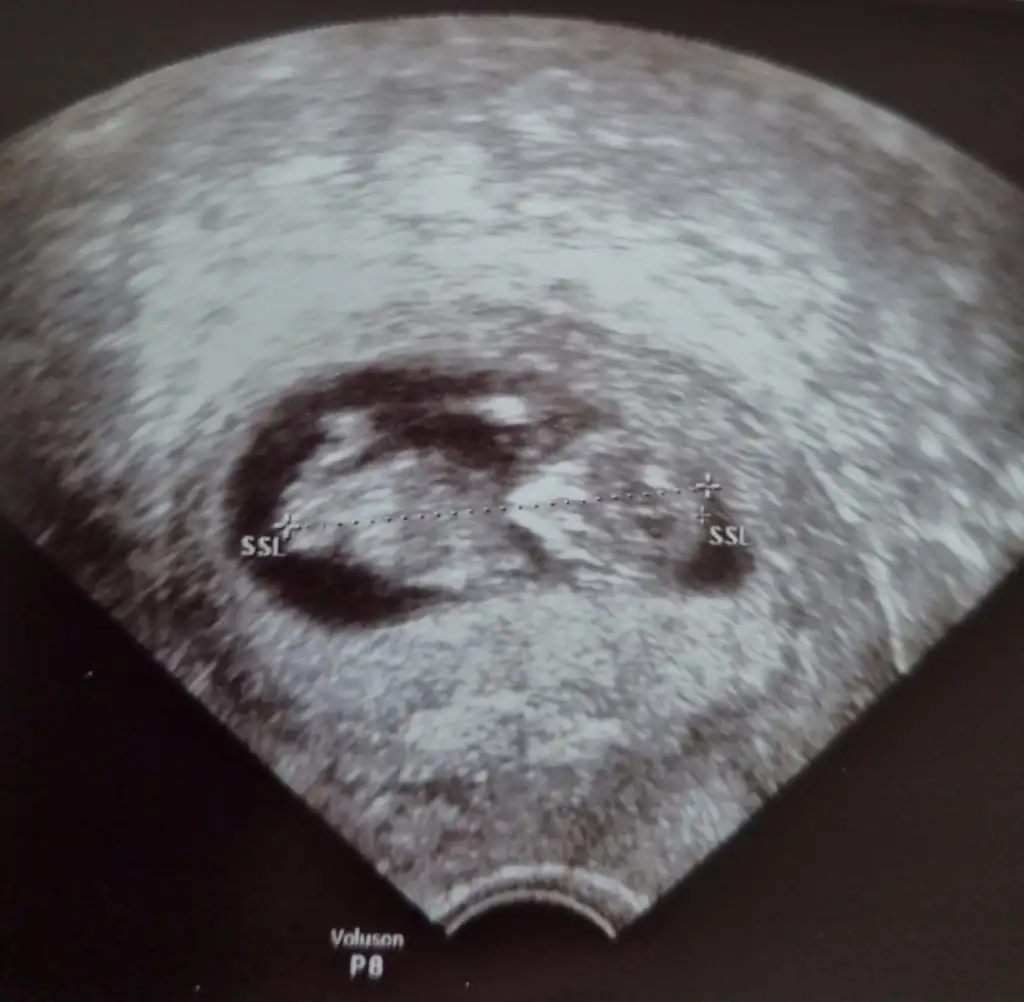

Net değil ama kız sanki başka USG varsa paylaşın 11 12 13 haftalar olmalıTahminlerinizi alabilirmiyim??? 12. Haftadan resim

Net değil ama kız sanki başka USG varsa paylaşın 11 12 13 haftalar olmalı

Ben size yazmıştım kız dedim diğer konudaBana ısrarla bakmadınız 12 hafta karından![]()

Ben size yazmıştım kız dedim diğer konuda